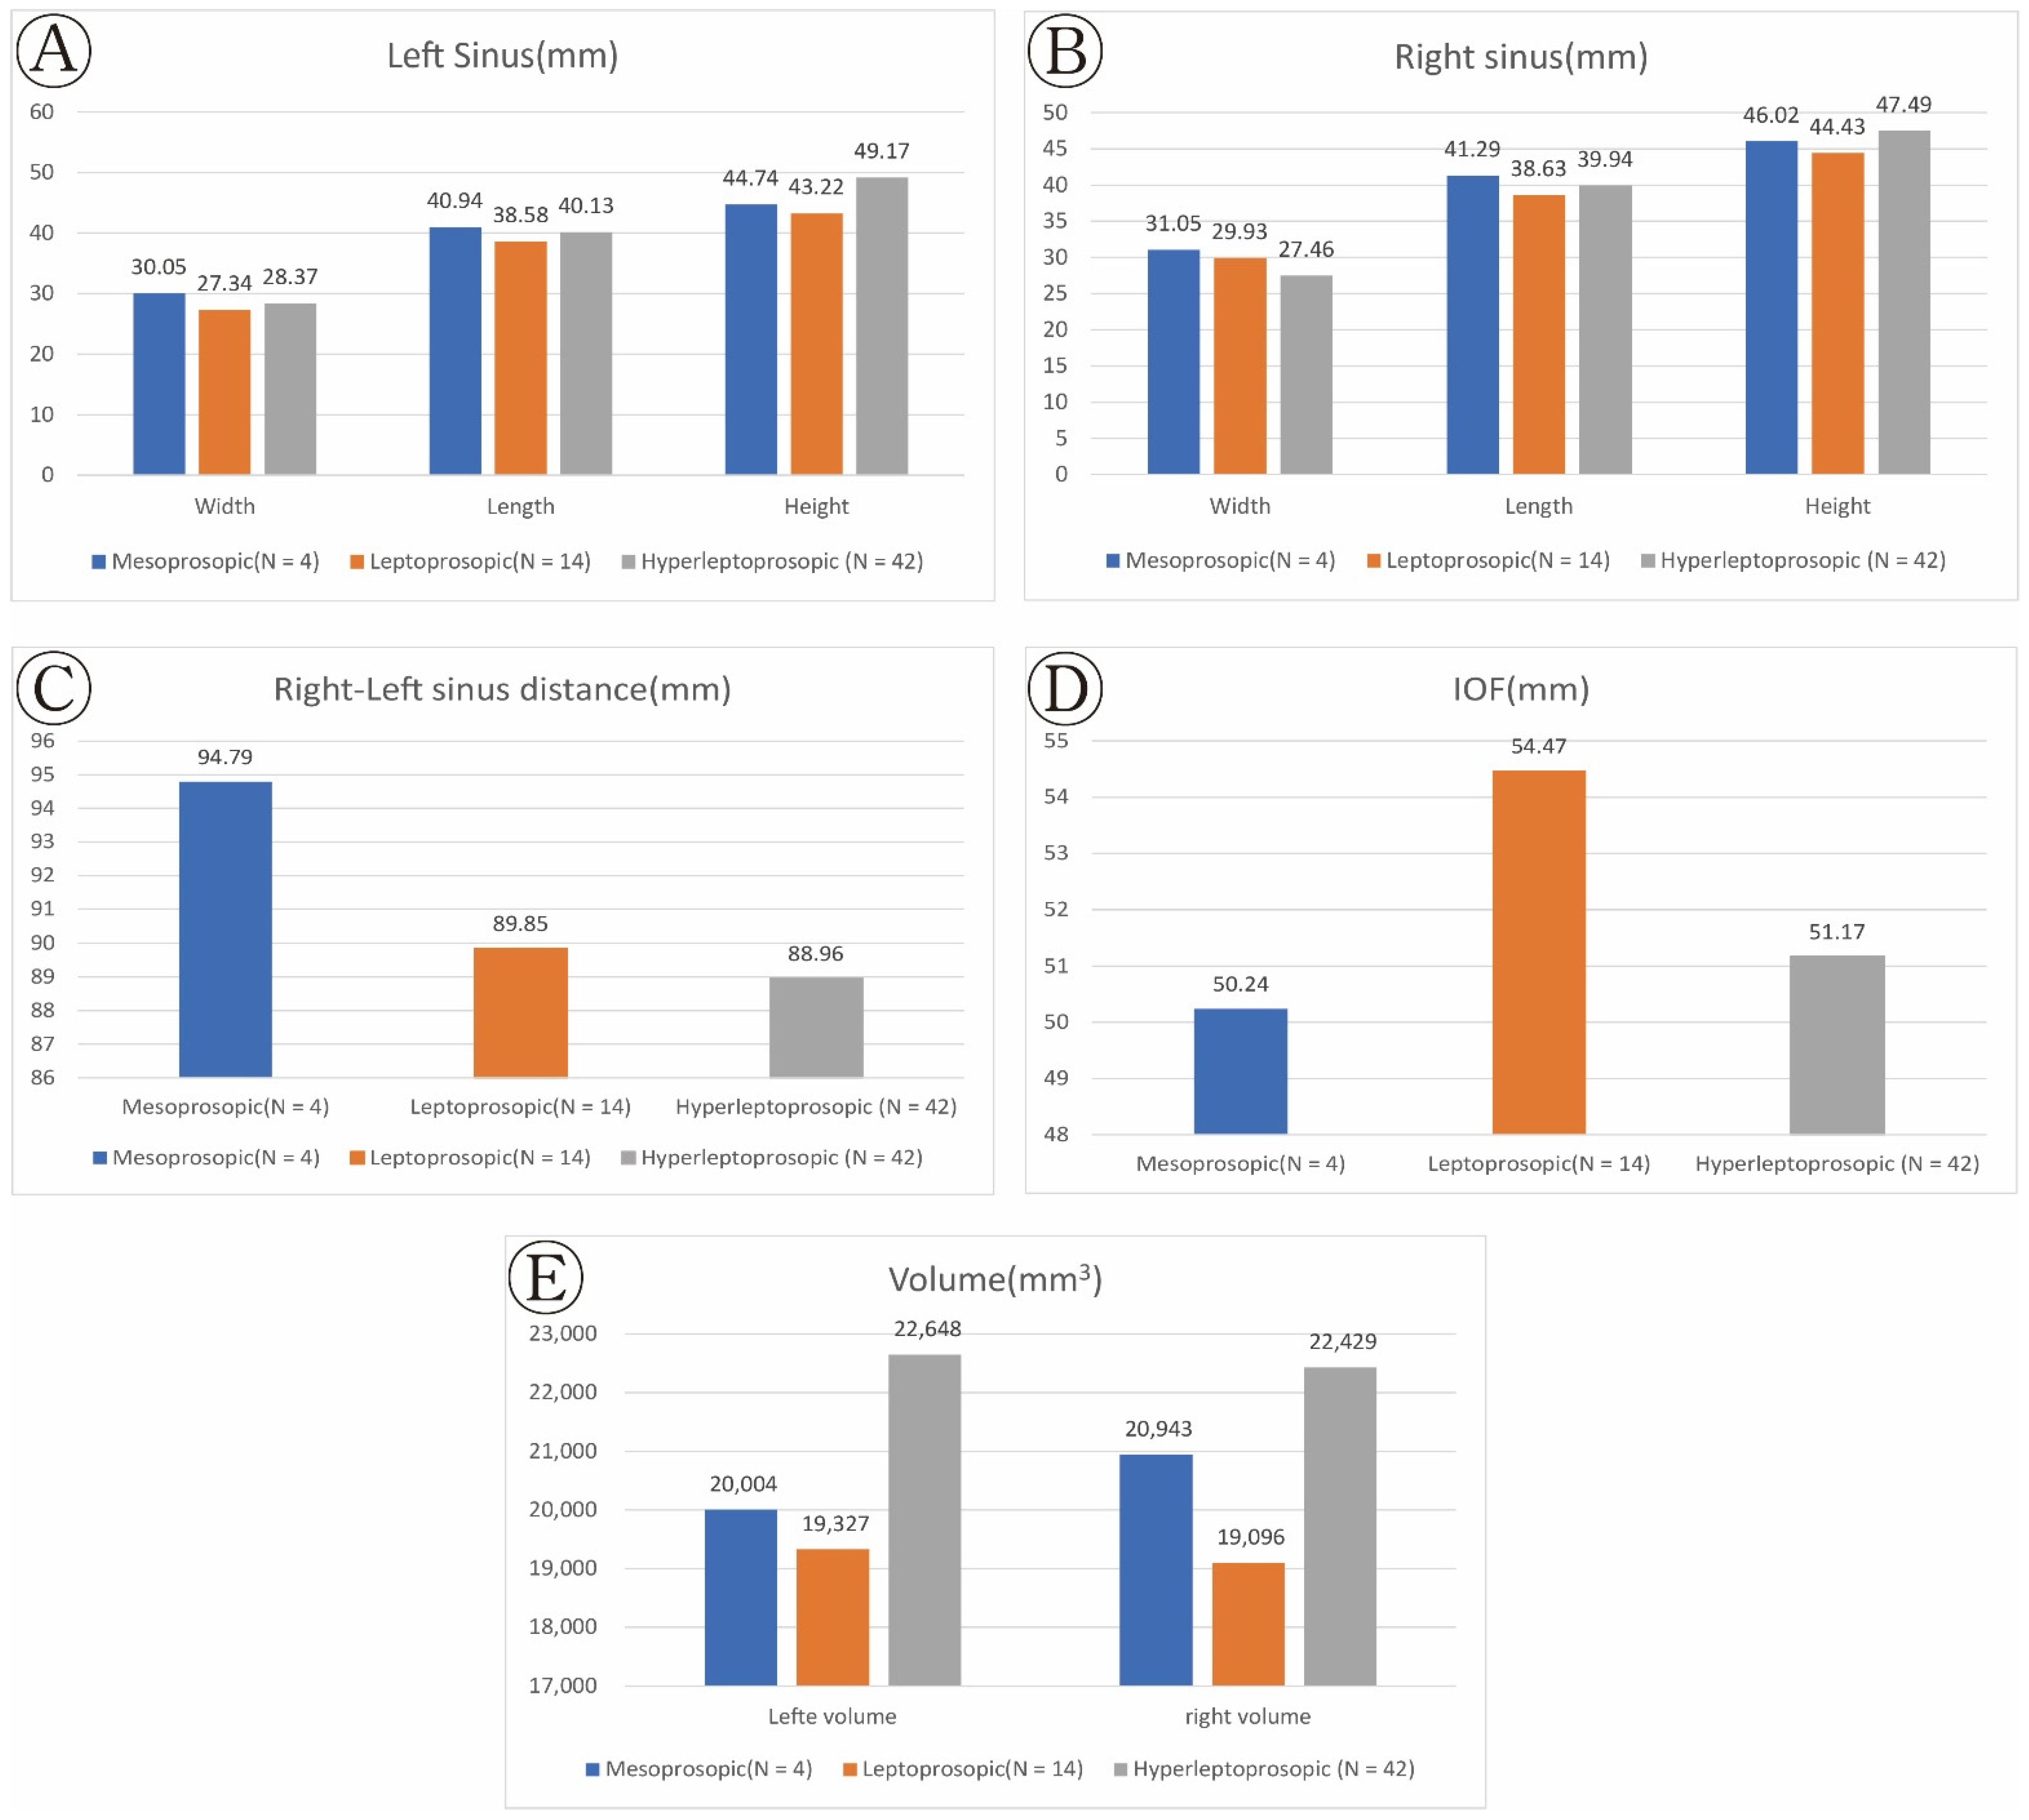

| Measurements | Mesoprosopic (N = 4) | Leptoprosopic (N = 14) | Hyperleptoprosopic (N = 42) | p-Value | |

|---|---|---|---|---|---|

| Right–left sinus distance (mm) | 94.79 (3.13) | 89.85 (6.66) | 88.96 (8.42) | >0.05 | |

| IOF (mm) | 50.24 (2.83) | 54.47 (5.42) | 51.17 (4.00) | <0.05 * | |

| (Left) | Width (mm) | 30.05 (1.28) | 27.34 (1.96) | 28.37 (1.87) | <0.05 * |

| Length (mm) | 40.94 (2.37) | 38.58 (3.51) | 40.13 (4.00) | >0.05 * | |

| Height (mm) | 44.74 (1.23) | 43.22 (2.88) | 49.17 (4.05) | <0.001 ** | |

| Volume (mm3) | 20,004 (2156.57) | 19,327 (3813.09) | 22,648 (4953.64) | <0.05 * | |

| (Right) | Width (mm) | 31.05 (1.91) | 29.93 (1.76) | 27.46 (4.47) | <0.05 * |

| Length (mm) | 41.29 (1.10) | 38.63 (3.33) | 39.94 (4.32) | >0.05 | |

| Height (mm) | 46.02 (1.36) | 44.43 (1.48) | 47.49 (2.66) | <0.001 * | |

| Volume (mm3) | 20,943 (1414.81) | 19,096 (1219.49) | 22,429 (4086.48) | <0.05 * | |